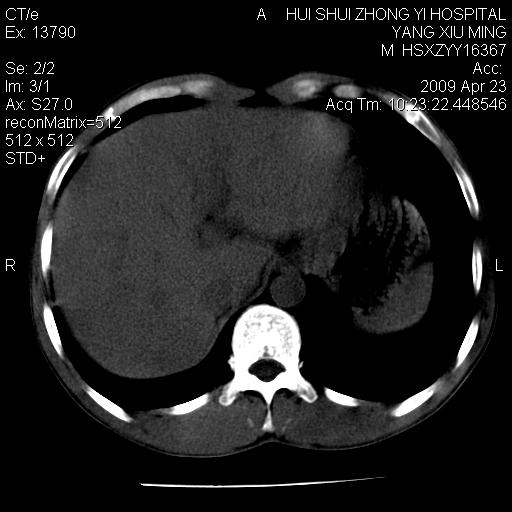

上腹部疼痛一月,呕吐10天,发现左侧颈部包快10天 胸部cr片未见明显异常。

腹膜后淋巴结增大,转移、淋巴瘤?胰腺增大,胰腺炎?占位?颈部考虑增大淋巴结。建议腹部增强扫描。

连最基本的ct值都没有测        腹部的窗宽窗位太大了     影响诊断

黑!广泛淋巴结肿大不符合胰腺癌转移。胰腺周围淋巴结肿大致使胰腺看起来大。考虑淋巴瘤可能大。